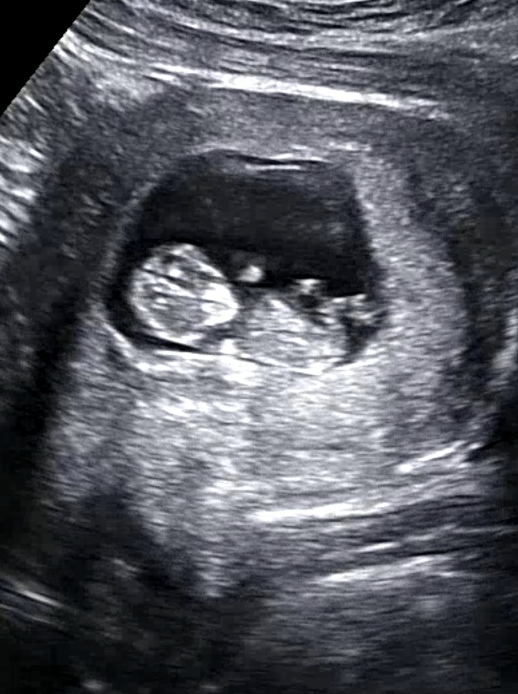

점점 커갈때마다 임산부는 힘들어하고 아기도 걱정되고 심하게 배가 땡기고 아플때마다 병원을 방문했습니다. 조금씩 출혈이 초음파에서 잡히기도 했고 의사선생님께서는 계속 눕거나 안정을 취해야 한다고만 하셨습니다. 토를 안하려고 신맛이 나는 사탕,젤리를 자주 먹었지만 갑자기 나오는 토는 참을수가 없습니다. 밖에 나갈때는 비닐이 필수였습니다.